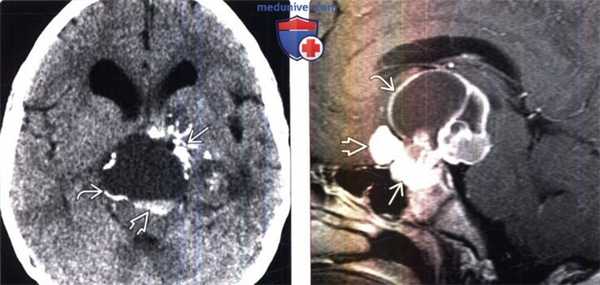

(Слева) Бесконтрастная КТ, аксиальный срез: классические признаки краниофарингиомы. Обратите внимание на крупную супраселлярную кисту с уровнем раздела жидкость-жидкость, ободком и глобулярными кальцификатами.

(Справа) МРТ, постконтрастное Т1 -ВИ, сагиттальный срез: в супраселлярной области определяется кистозное объемное образование сложного строения; отмечается контрастирование ободка и солидных компонентов опухоли. Кисты содержат жидкость различной интенсивности сигнала. Обратите внимание на крупный супраселлярный и более мелкий интраселлярный компоненты этой классической краниофарингиомы.